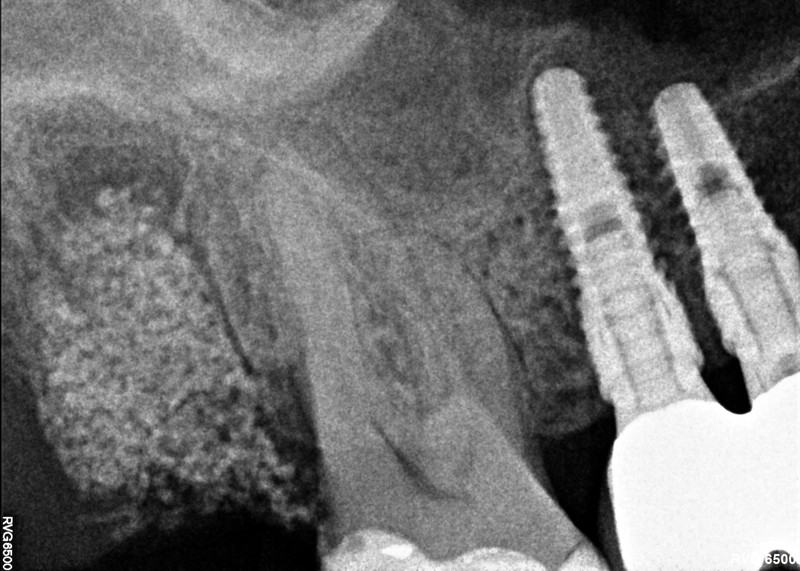

OK 17

Entfernung Zahn 17, Augmentation DentOss grob, 6 und 9 Tage danach, Situation + RÖ.